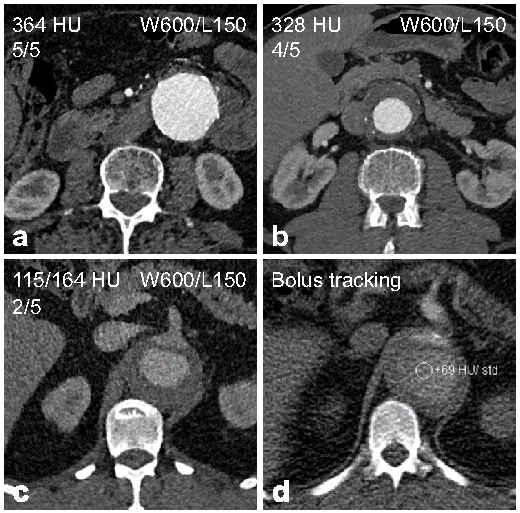

| Rating | Description |

| Excellent (5) | Aorta and iliac arteries with excellent enhancement and little noise. |

| Good (4) | Aorta and iliac arteries with good enhancement and little to moderate noise. |

| Moderate (3) | Aorta or iliac arteries partially with low to moderate enhancement and/or moderate to high noise. |

| Fair (2) | Aorta and iliac arteries completely with low enhancement and/or high noise. |

| Non-diagnostic (1) | Aorta or iliac arteries partially with insufficient enhancement and/or disruptive noise. |

| Rating | All Patients n = 161 | Group A (BMI < 30 kg/m2) n = 126 | Group B (BMI ≥ 30 kg/m2) n = 35 |

| Average * | 4.5 ± 0.6 | 4.6 ± 0.5 | 4.1 ± 0.9 |

| Excellent | 78 (48.4) | 69 (54.8) | 9 (25.7) |

| Good | 66 (41.0) | 49 (38.9) | 17 (48.6) |

| Moderate | 13 (8.1) | 8 (6.3) | 5 (14.3) |

| Fair | 3 (1.9) | 0 (0) | 3 (8.6) |

| Non-diagnostic | 1 (0.6) | 0 (0) | 1 (2.9) |